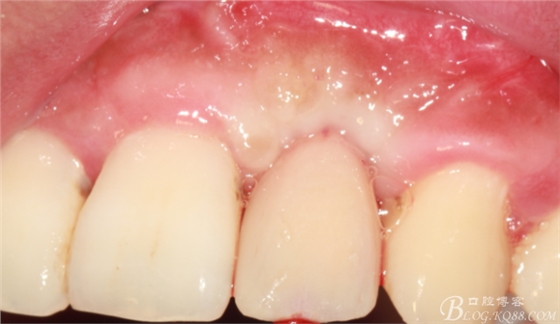

事實(shí)證明,我的做法沒有錯(cuò)誤,一個(gè)月后,軟組織健康愈合。鄰牙軟組織沒有退縮。

再次翻瓣。